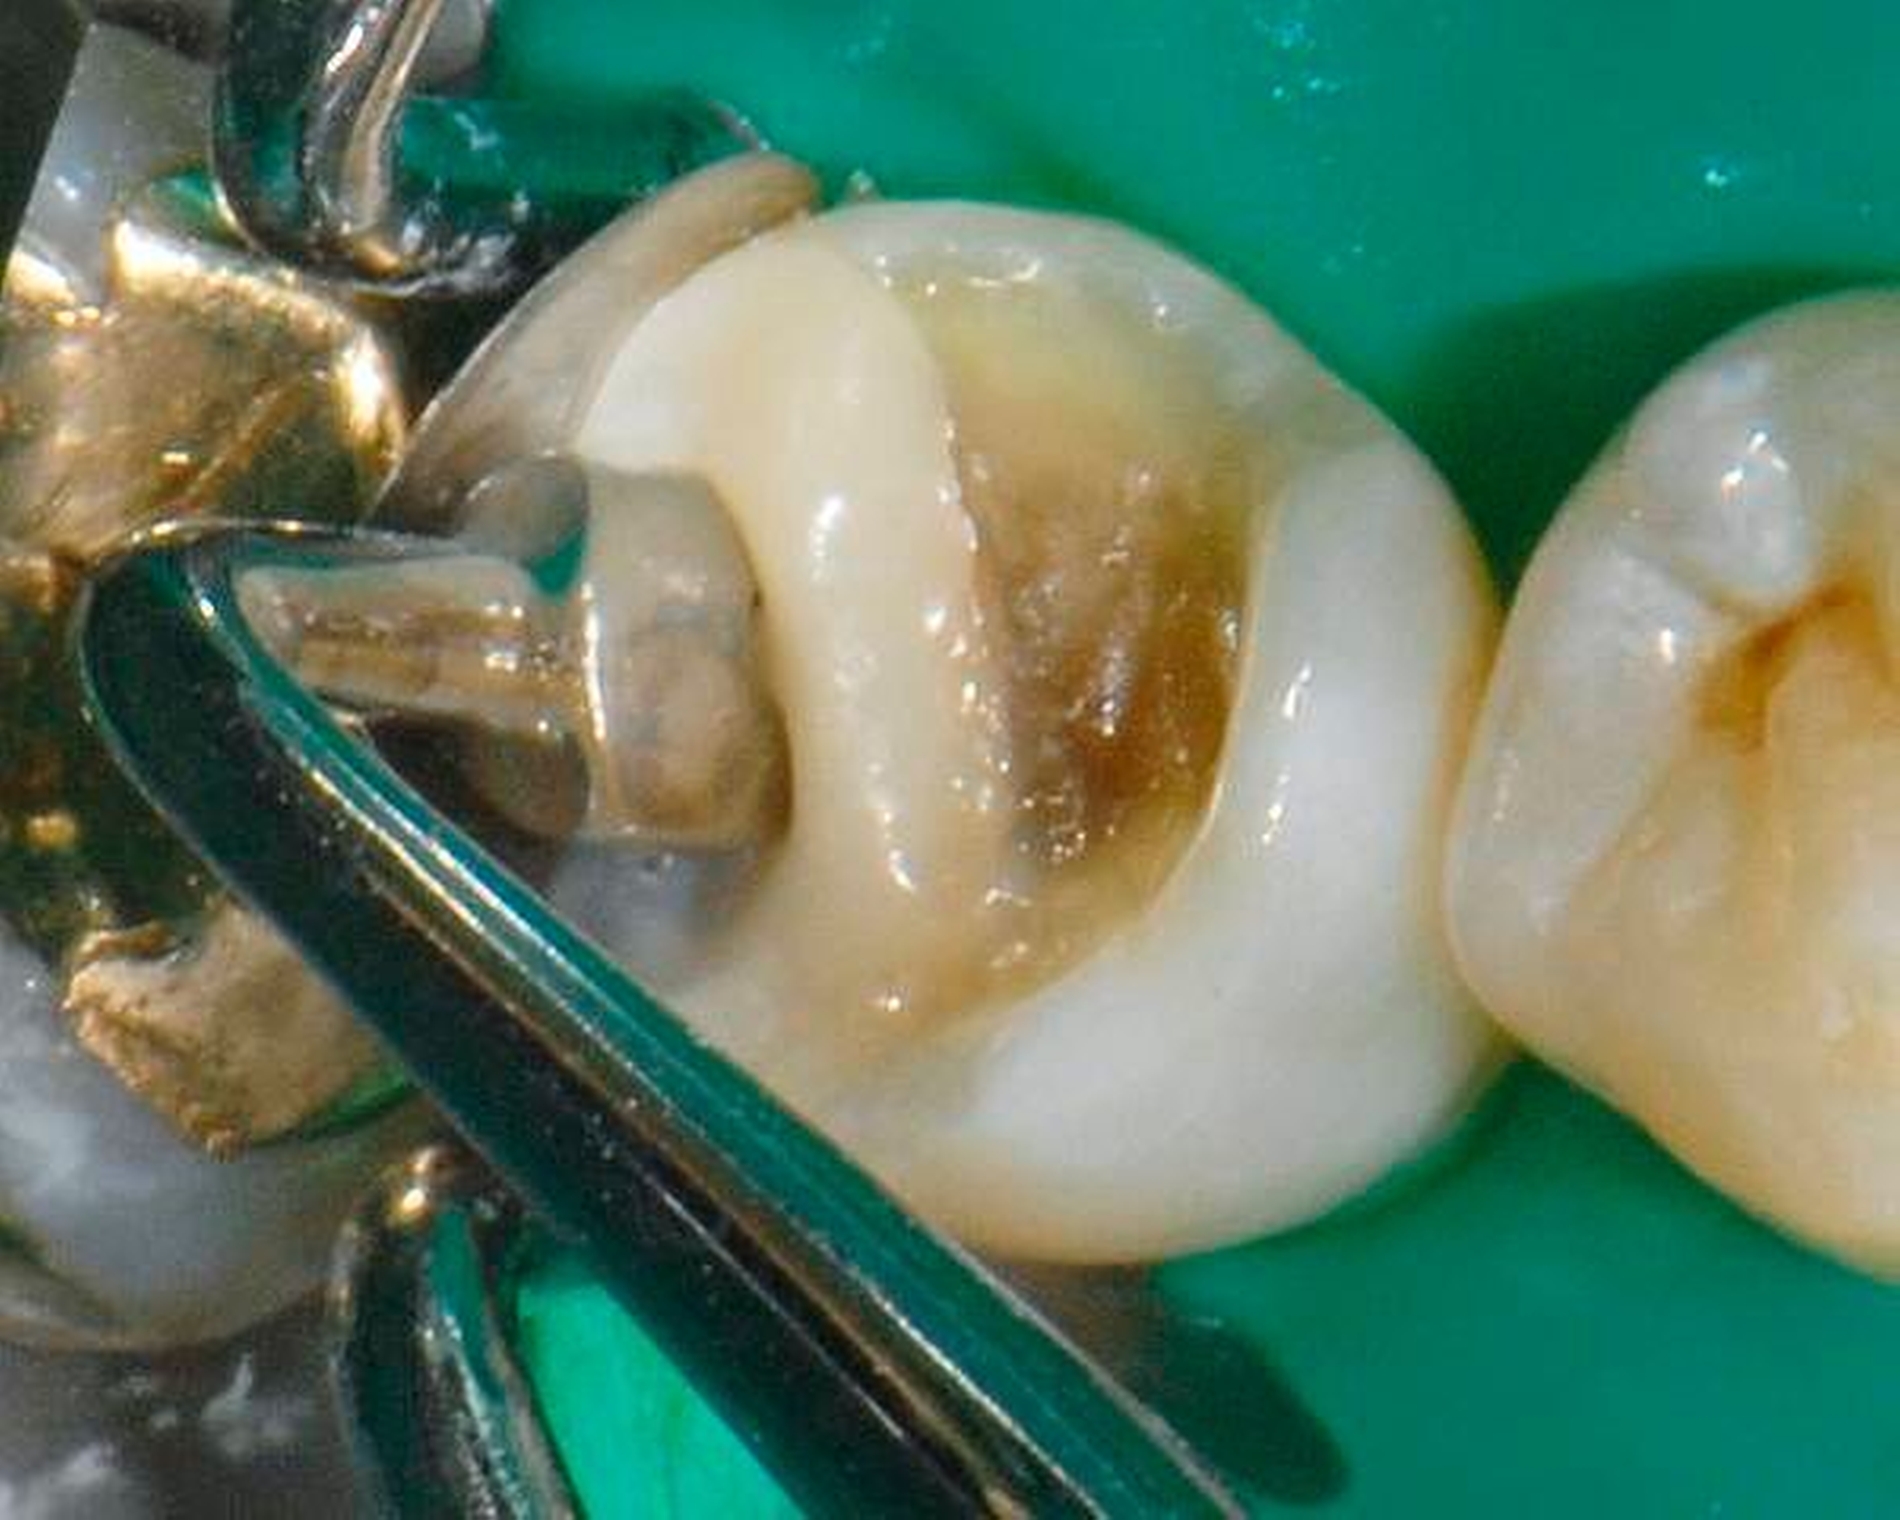

Abbildung 3: Direkte Reparatur im Seitenzahnbereich (R2-Technik)

In den Abbildungen 1 bis 3 werden Optionen für frugale Interventionen auf restaurativem Sektor aufgeführt. Es handelt sich um direkte Vollüberkronungen im Frontzahnbereich (hier: hergestellt in R1-Technik / einphasig) (Abbildung 1), direkte Teilüberkronungen im Seitenzahnbereich (hier: hergestellt in R1-Technik / einphasig) (Abbildung 2), Reparatur-Restaurationen im Seitenzahnbereich (hier: hergestellt in R2-Technik / zweiphasig) (Abbildung 3). Technische Einzelheiten zur Vorgehensweise und den Ergebnissen sind an anderer Stelle beschrieben (Literatur siehe oben).

schadensgerechte Reparaturtechniken (Abbildung 3),